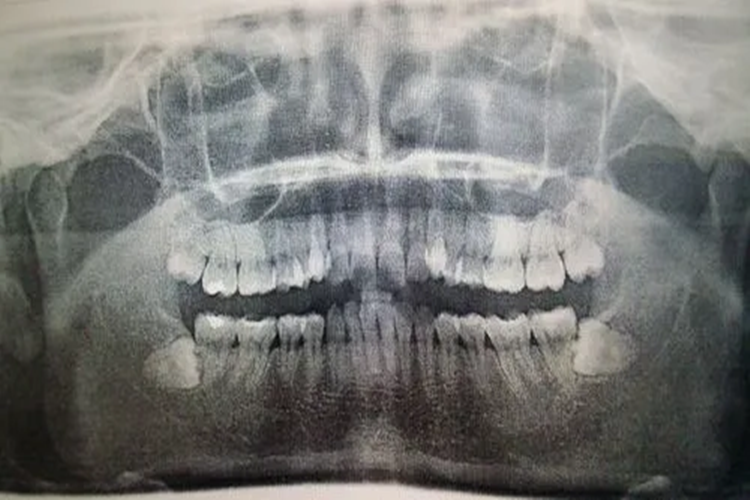

横向阻生智齿即水平阻生第三磨牙,该牙齿在颌骨内不能萌出到咬合位置,只有部分萌出或完全不萌出,通过X线影像学检查可见其长轴与第二磨牙长轴呈90°,牙根向远中弯曲或呈环抱状。